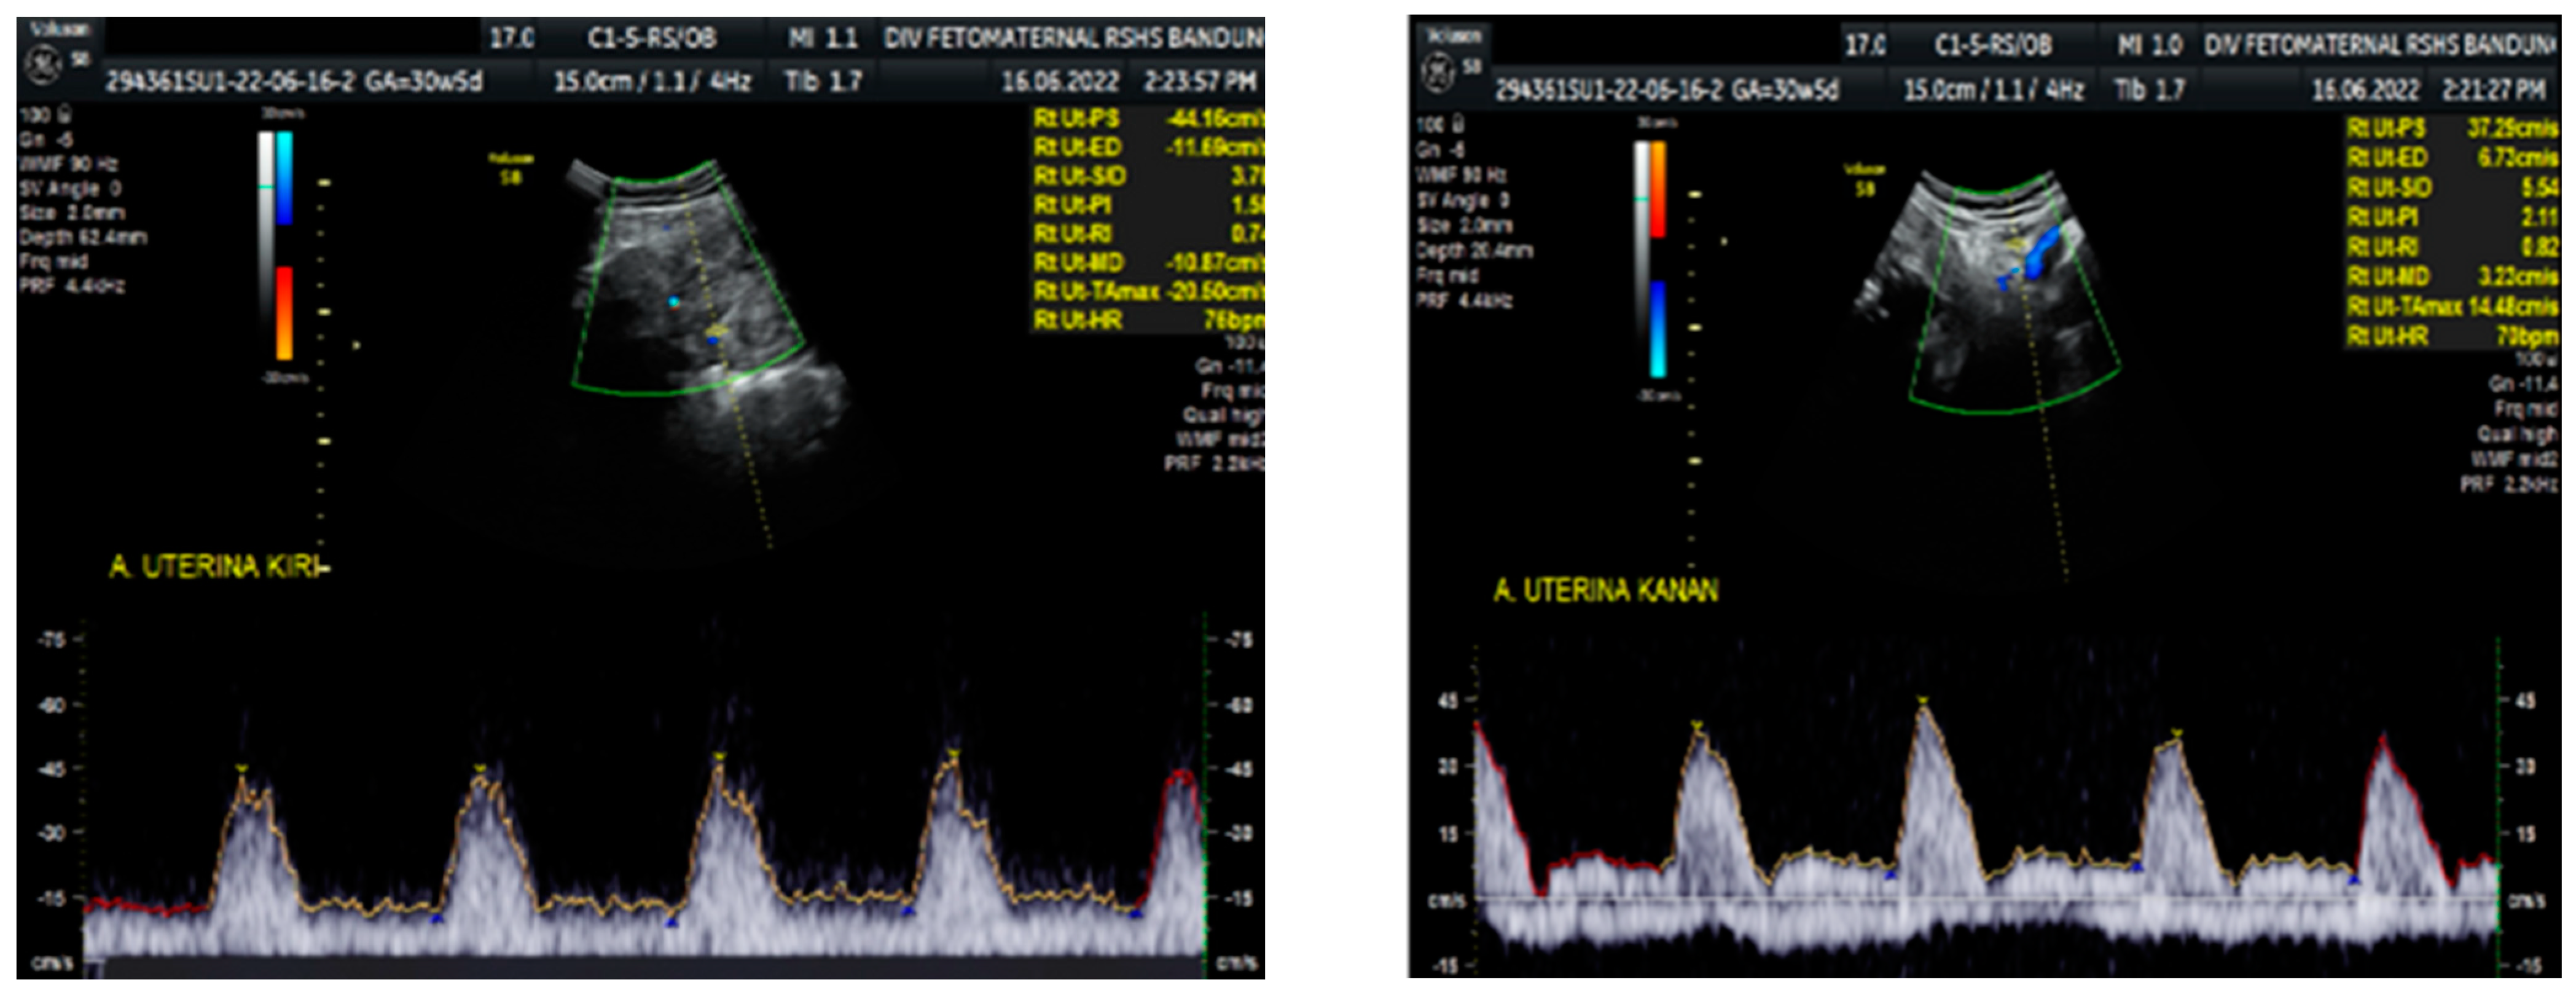

Figure 3. Notching on right and left uterine artery Doppler.

Color Doppler examination of the MCA revealed a peak systolic velocity of 42.33 cm/s, which is 1.045 times the median (the normal range is 40.5 cm/s for this gestational age), with persistent reversed end diastolic flow (Figure 2). The umbilical artery pulsatility index (PI) was 0.99, and RI was 0.63, with an S/D ratio of 2.71. There was notching on the right uterine artery, with a PI of 2.11. Notching was also found on the left uterine artery, with a PI of 1.58 (Figure 3). Laboratory results were within a normal range.

The Doppler examination also revealed a notching of the right and left uterine arteries, which is a marker of spiral artery remodeling failure, causing early-onset severe preeclampsia [11,12]. In this case, inadequate early prevention worsened the patient’s condition, leading to severe preeclampsia. The pregnancy did not present with hydrocephalus, cerebral hemorrhage, or mechanical compression of the fetal head. Another anatomical abnormality cannot be assessed intrauterine, nor seen after delivery. We did not perform a postnatal examination to exclude any internal neonatal anatomy abnormalities.